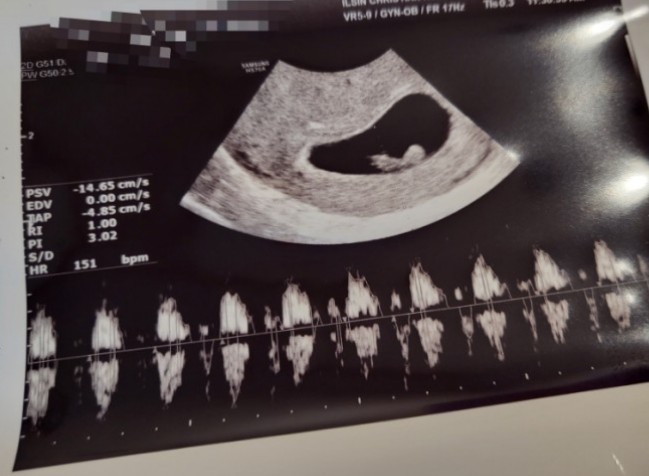

안녕하세요! 이제는 곰곰이맘이 된 쭈짱이에요! 저도 어느새 임신 7주차가 되었고 불과 몇 달 전만 해도 제...

난임 끝에 임신 성공후기 및 좋았던 것들 총정리(난임병원,활기담 장어즙,반신욕)

안녕하세요!! 뚀이맘이에요! 드디어 난임 걱정 끝에 임신을 했어요!!! 어느새 임신 6주차가 되었는데요..! ...